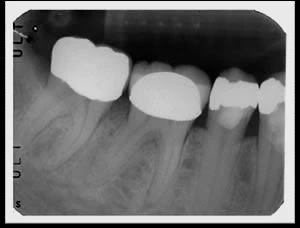

Bệnh nhân nam được chuyển tới phòng khám của tôi kèm theo 1 phim cận chóp (Hình 1). Thông tin từ bác sĩ trước đó cung cấp bao gồm cơn đau thể hiện dấu hiệu của viêm tủy không hồi phục kèm theo vấn đề ở cuống răng. Có thể thấy dây chằng nha chu ở chân gần dày lên, nhưng chụp răng trông khá tốt.Thêm một vấn đề là tôi thấy phim tham khảo này có hình ảnh có vẻ hơi ngắn.

Hình 1: Phim cận chóp ban đầu.

Phim cận chóp ban đầu cho thấy đường viền phía gần của răng không đồng đều. Vì tấm phim được chụp không sử dụng cây định hướng tia nên tôi nói với trợ lý của mình tôi cảm thấy hình ảnh trên tấm phim này vẫn hơi ngắn.Sau khi sử dụng phim cánh cắn (Hình 2) những nghi vấn của tôi đã được giải đáp. Bên dưới chụp răng có sâu lớn, xác định được bằng thăm khám trên miệng.